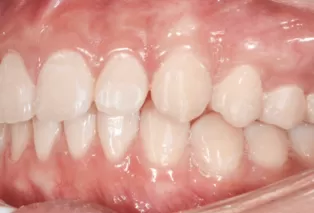

Photos intra-orales

teeth straightening aligners 4

teeth straightening aligners 5

teeth straightening aligners 6

teeth straightening aligners 7

teeth straightening aligners 8